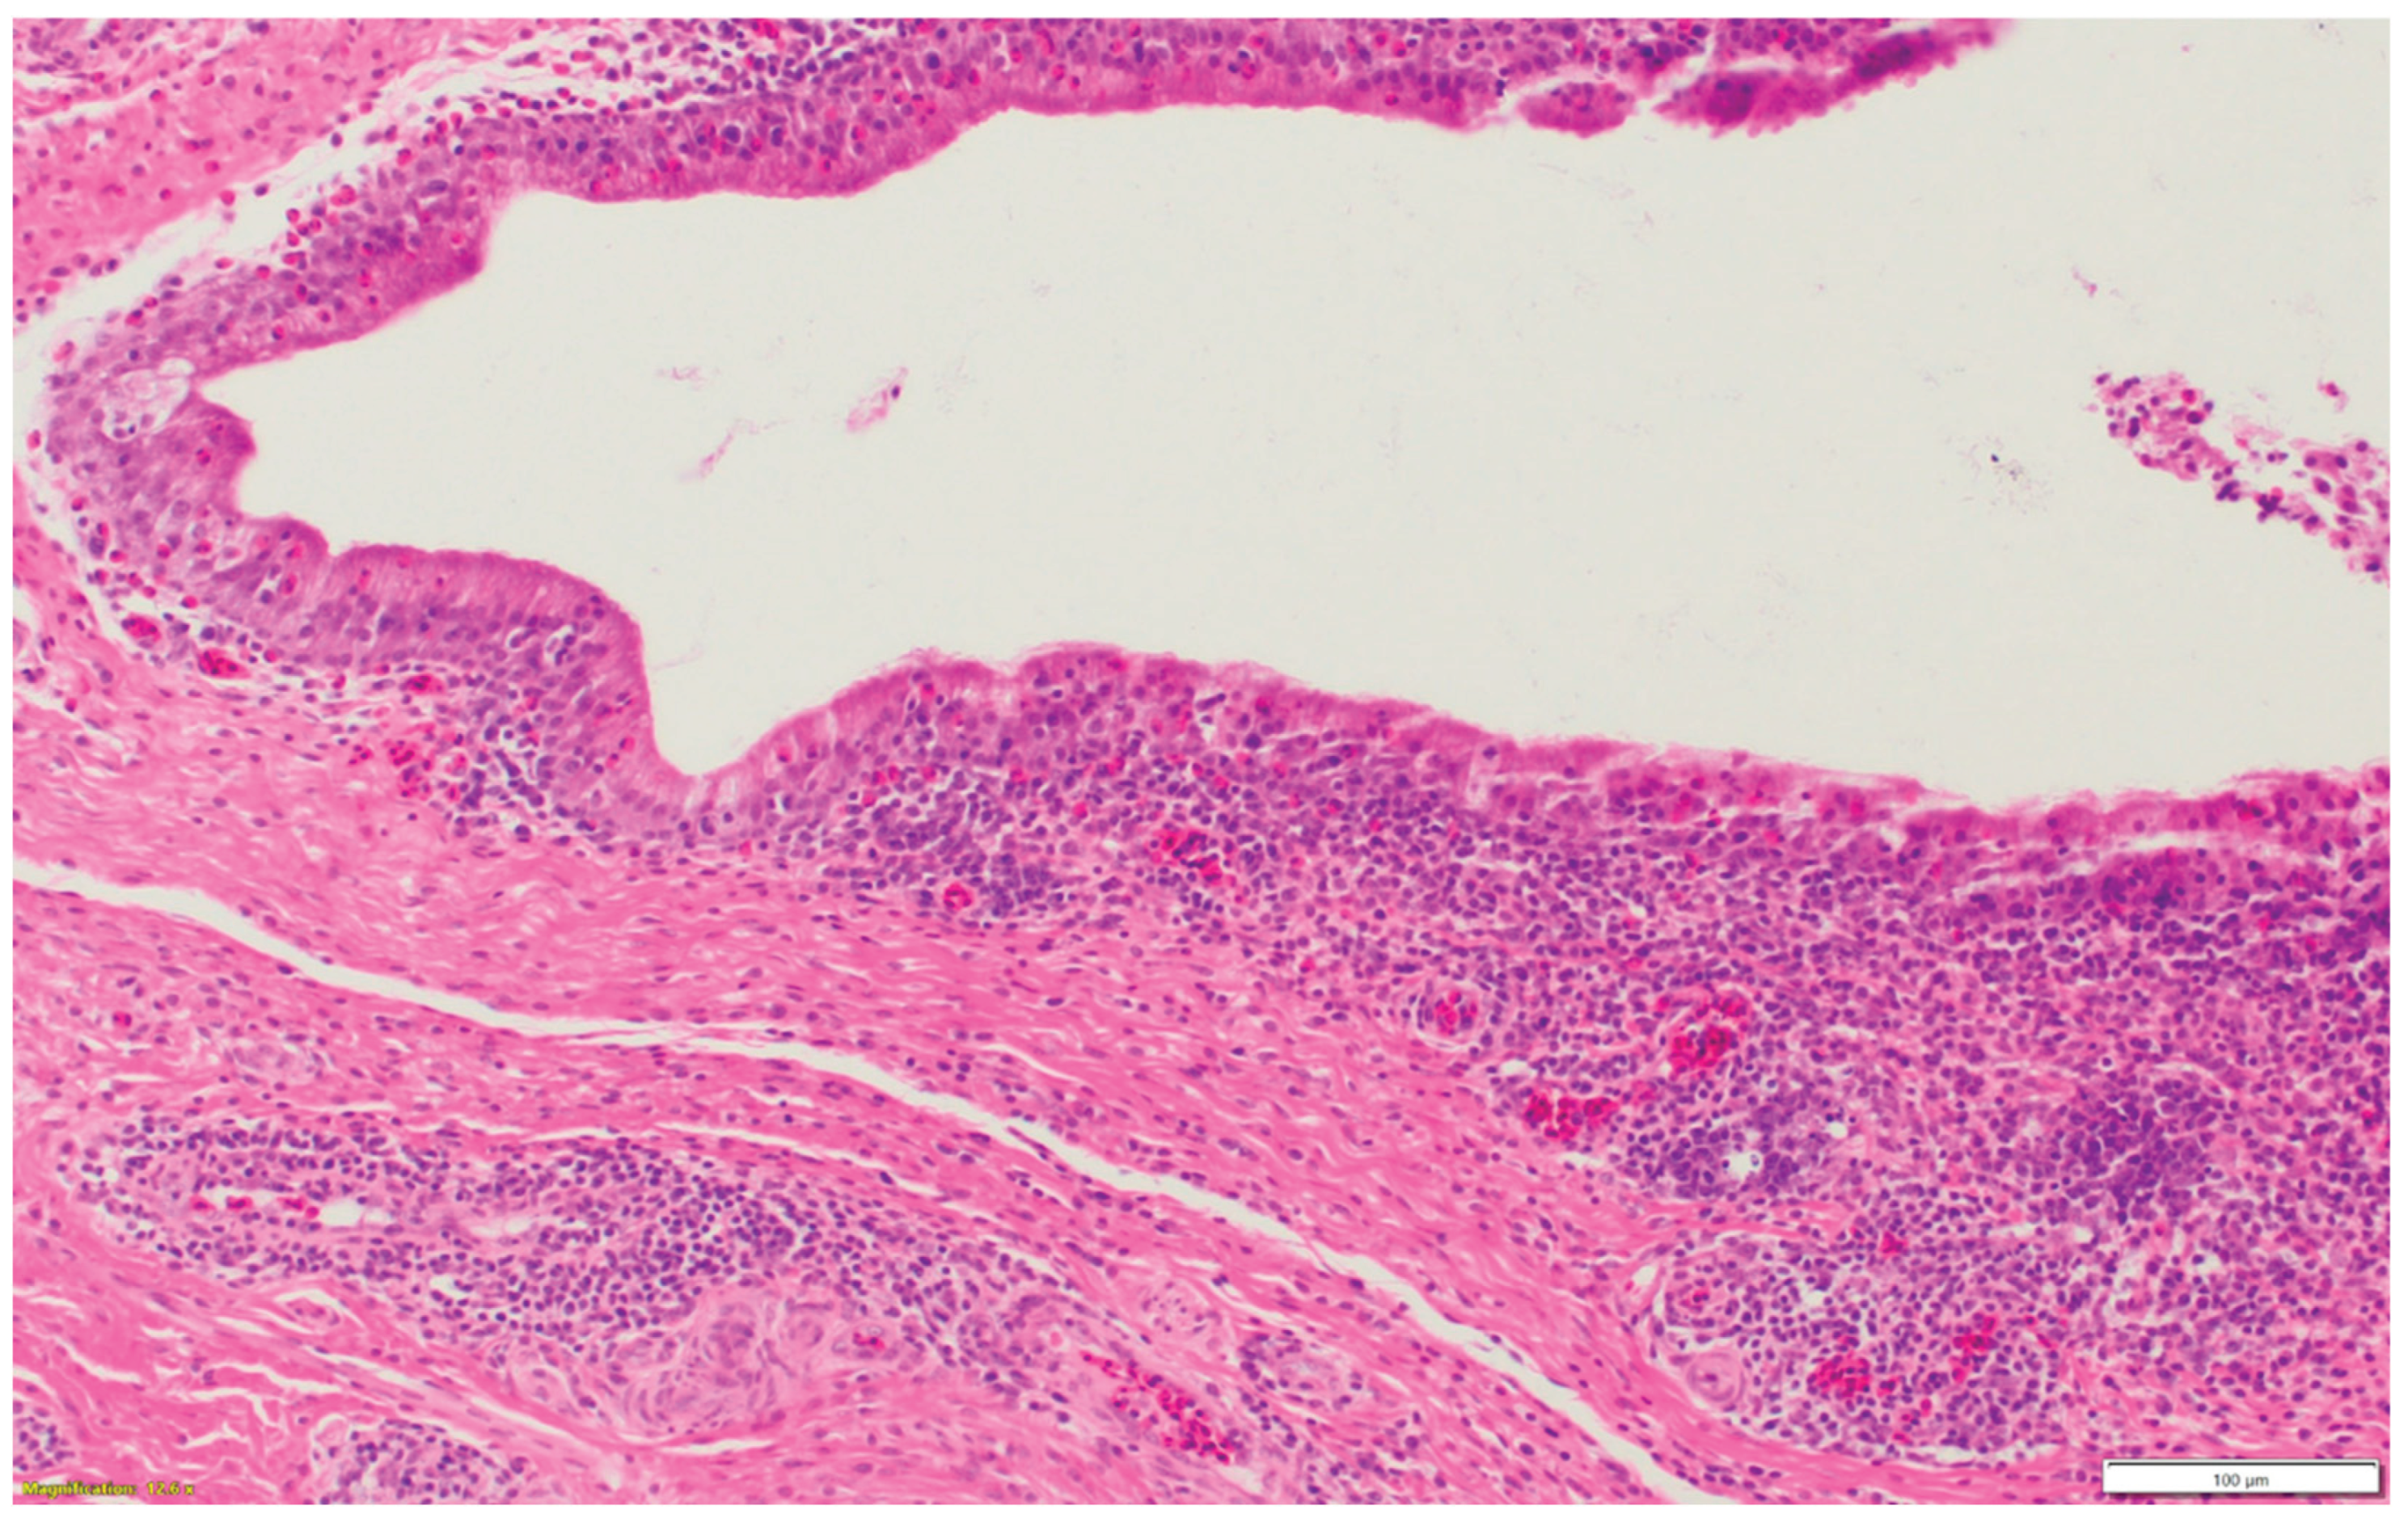

3.1. Turkeys infected with aMPV at 1-day-old (Figure 2a) had a higher total HRI compared with noninfected controls. The gap between the two groups increased significantly as the birds aged. Sinus and eyelid scores were the main contributors to the difference between the control and infected groups. A similar pattern was observed in groups inoculated at 7- and 14-day-old (Figure 2 b-c), but with higher scores. Sinus was the central part of the score difference, followed by the eyelids.

3.2. Chickens infected with aMPV at 7- and 14-day-old (Figure 3a-b): A similar pattern to the turkeys inoculated with AMPV at 7- and 14-day-old. Similarly, sinuses and eyelids created the main difference between the control and infected groups.

3.3. Turkeys inoculated with aMPV at 7 days of age showed higher lesion scores at 10 DPI compared with the non-infected control group. Sinus and eyelids were the main organs scoring points compared with other organs (Figure 4a).

3.4. Turkeys inoculated with low pathogenic avian influenza (LPAI-H4N6) at 7 days of age had also increased histologic lesion scores at 7 DPI compared with the non-infected control group. Sinus, lungs, eyelids, and trachea were orderly contributing to a higher total HRI (Figure 4b).